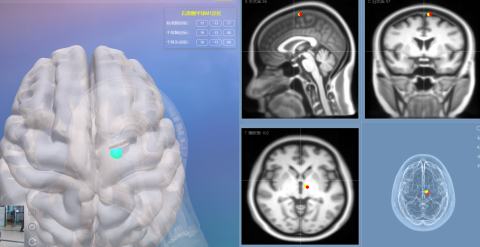

“导航”又是什么?传统的磁刺激有点像“模糊打击”,大概方向对,但不够精确。而我们的导航机器人,则实现了 “精确制导” 。它能结合您个人的大脑MRI影像,构建出您独一无二的“大脑地图”,然后引导磁刺激探头,以毫米级的精度作用于目标脑区,绝不“跑偏”。

建“地图”(首次治疗前):系统会生成您的3D“数字大脑”。

定“靶点”: 医生在“数字大脑”上精准选定需要治疗的区域。

开始治疗: 精准导航机器人引导经颅磁刺激到对应位置。

实时导航: 屏幕上实时显示探头位置,系统确保治疗全程“弹无虚发”。